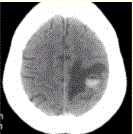

问题 患者女,55岁,右侧肢体无力3d。头颅CT显示如下图。 可能的诊断为(提示为进一步明确诊断,头颅CTA及CT灌注如下图(CBV未见血流量升高,CTA未见异常供血动脉)。

选项 A.急性脑血肿 B.转移瘤伴出血 C.胶质瘤伴出血 D.少枝胶质细胞瘤伴出血 E.血液系统病变伴脑出血 F.脑脓肿 G.血管畸形伴出血

答案 ABE